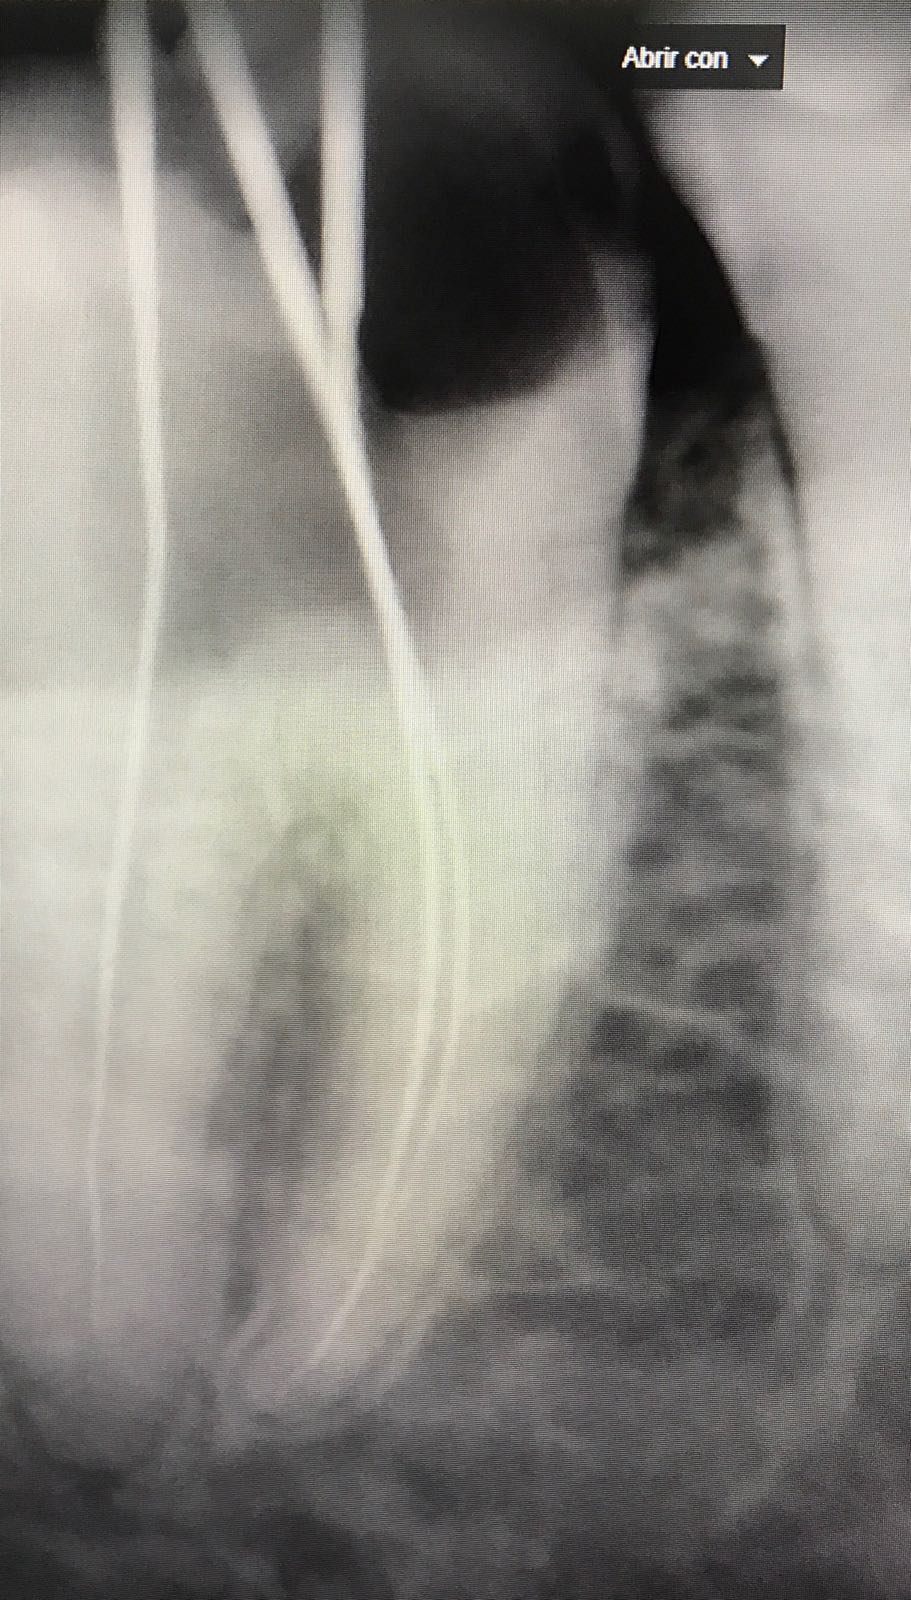

En esta fotografía observamos la apertura de la cámara pulsar.